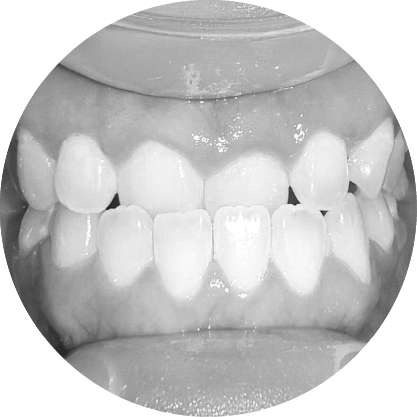

ตัวอย่างในชีวิตจริง